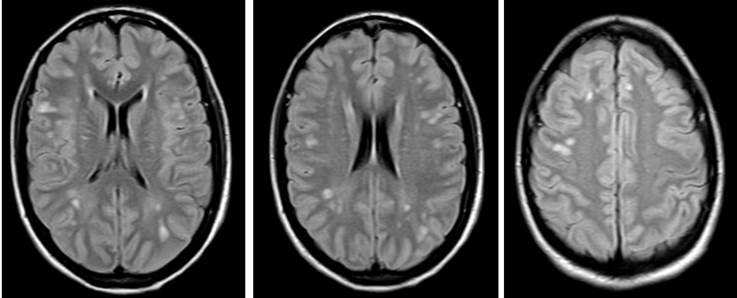

Respecto a las ayudas imagenológicas, se realizó una tomografía simple de cráneo que evidenció lesiones focales hipodensas en sustancia blanca periventricular de aspecto inespecífico sin efecto de masa (Figura 1); dado que estos hallazgos no descartaron neuroinfección, se llevó a cabo un estudio de líquido cefalorraquídeo que no reportó alteraciones. Posteriormente, se ordenó una resonancia magnética nuclear de abdomen que detectó hígado aumentado de tamaño y disminución de la intensidad de señal de manera difusa por infiltración de grasa hepática; además, en el segmento VIII se observó lesión focal hepática hipervascular de contornos lobulados, forma irregular y diámetro de 13x11x13 cm, con compresión de venas suprahepáticas, vena cava inferior y vena porta intrahepática izquierda con compresión de la vía biliar intrahepática (Figura 2). Dado el hallazgo de masa hepática, se decidió tomar biopsia de la lesión, cuyo reporte histopatológico fue compatible con FL-CHC (Figura 3).

Figura 1 Tomografía simple de cráneo en paciente con hiperamonemia y carcinoma fibrolamelar.

La paciente reportada debutó con síndrome convulsivo asociado a niveles elevados de amonio y no presentaba antecedentes de consumo crónico de alcohol ni estigmas de hepatopatía crónica o electrolitos, además su perfil metabólico era normal; sin embargo, llamaron la atención los cambios estructurales a nivel de tomografía cerebral concordantes con los cambios fisiopatológicos que ejerce el amonio en el cerebro.